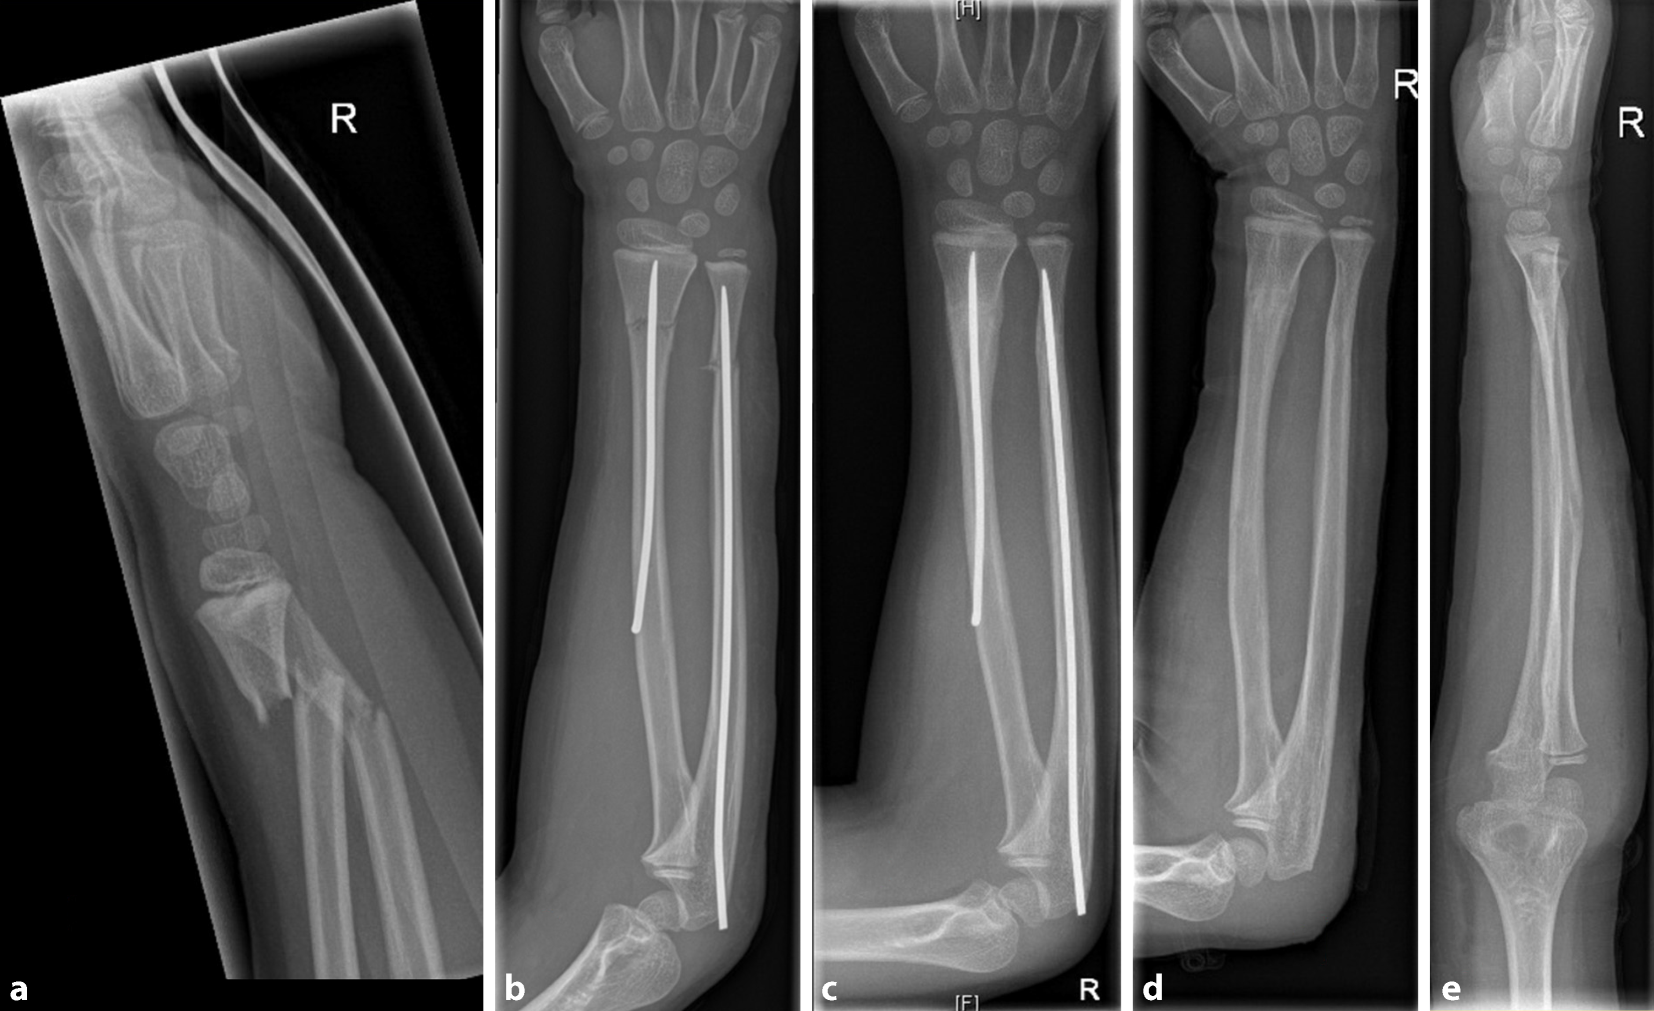

Abb. 8

Fall eines 7‑jährigen Jungen nach Sturz vom Klettergerüst auf den rechten Arm und radiologische Darstellung einer diametaphysären Unterarmfraktur (a). Postoperatives Röntgenbild nach antegrader TEN-Osteosynthese (b). Regelrechte Konsolidierung nach 3 Monaten (c). Verheilte Fraktur in regelrechter Stellung nach Metallentfernung (d, e)